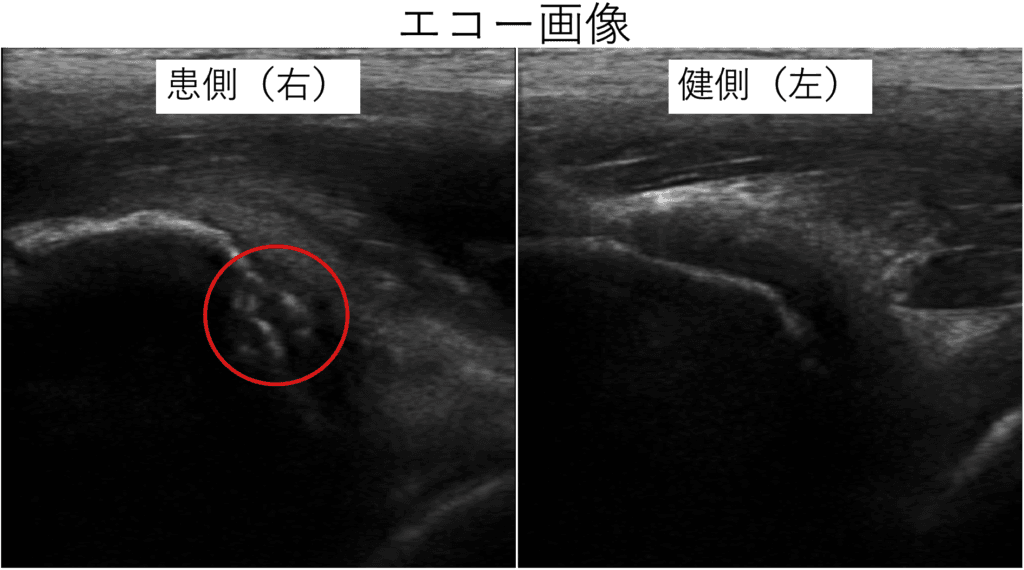

初診時のエコー検査は、次の写真となります。

エコー検査にて下前腸骨棘の裂離骨片像が確認できたため、「下前腸骨棘裂離骨折」と判断し、直後に連携している整形外科に紹介してレントゲン検査をしていただきました。